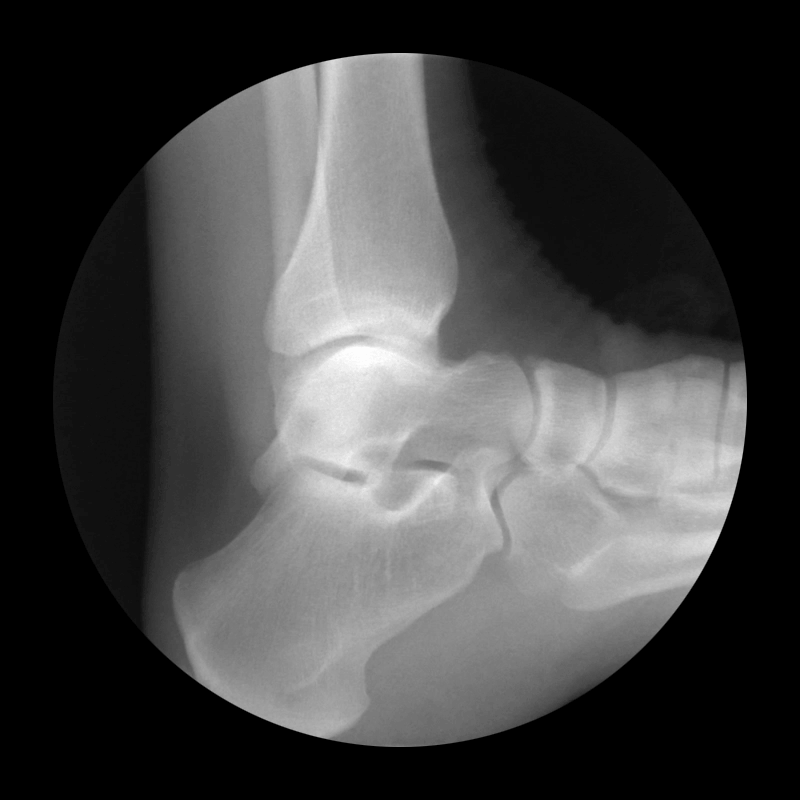

Foot